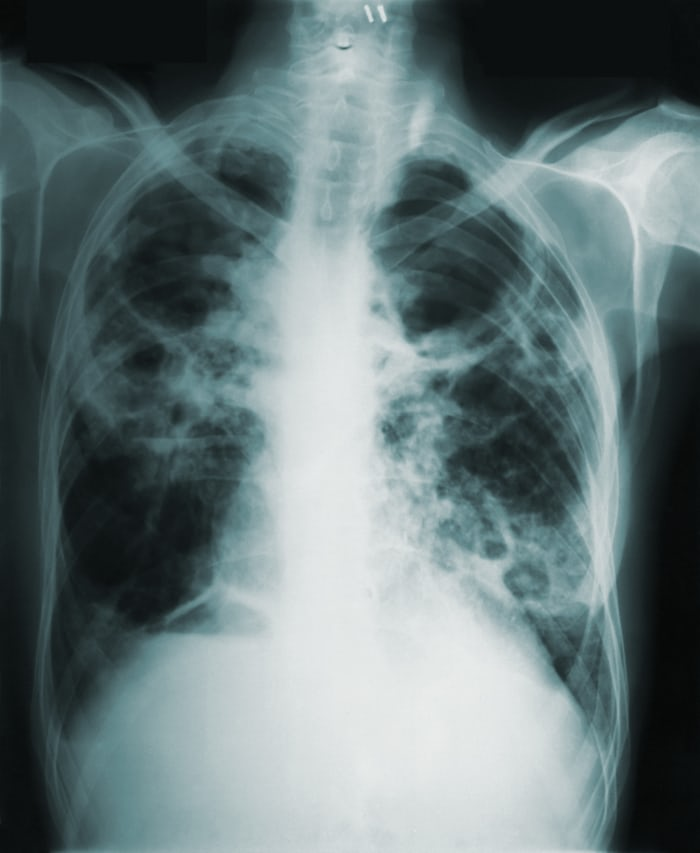

- 진단: 폐질환의 진단은 X-레이, CT 스캔, 혈액검사 등을 통해 이루어집니다.

폐질환의 전망 폐질환의 치료 방법 및 연구 동향이 더 발전되어 환자들에게 더 나은 치료 옵션을 제공할 것으로 기대됩니다. 이는 폐질환 환자들의 생존율 및 삶의 질을 향상시킬 것으로 전망됩니다.폐질환의 진단과 치료에 대한 연구는 끊임없이 진행되고 있습니다. 폐암의 조기 진단을 위한 검사 방법이 더욱 정교해지고 있으며, 최신 기술인 인공지능을 활용한 진단법도 연구되고 있습니다. 또한, 폐렴이나 만성폐쇄성폐질환을 치료하기 위해 투석 치료나 치료제 등의 방법도 개발되고 있습니다. 이러한 연구 동향과 전망을 요약하면 다음과 같습니다:

- 폐암의 조기 진단을 위한 다양한 검사 방법이 개발되고 있다.

- 인공지능을 활용한 진단법이 주목을 받고 있다.